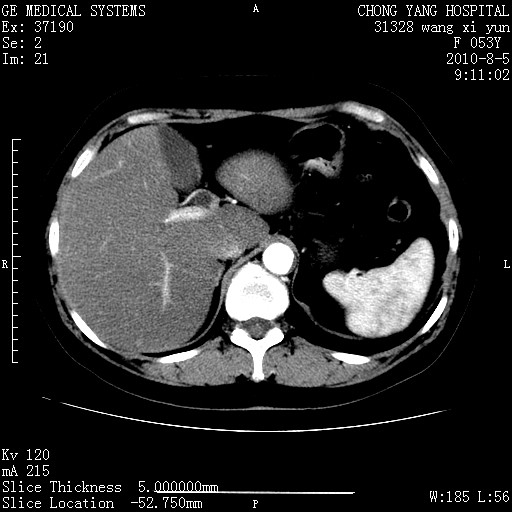

标题: CT28214:F41Y 血尿二十天,建议盆腔平扫加增强。

1)考虑肝左叶胆管细胞癌。2)脂肪肝。